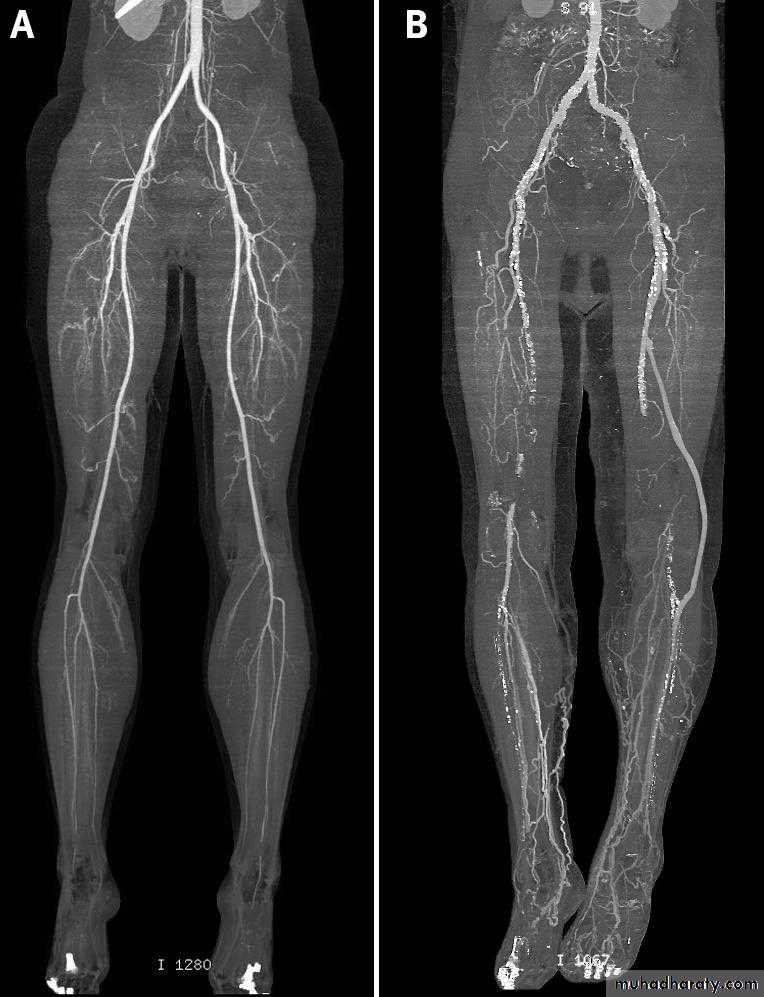

Fig 4 Computed tomography angiograms showing (A) normal lower limb vasculature and (B) heavily diseased arteries with

previous left femoral anterior tibial bypass